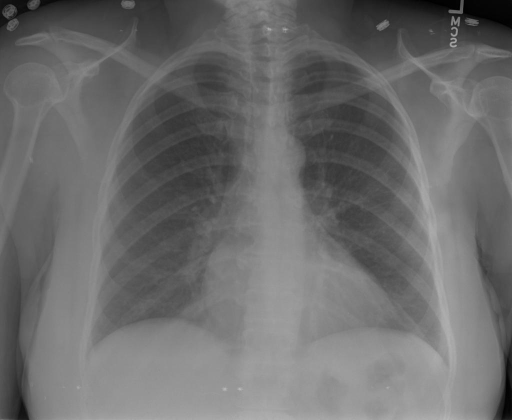

- (1)准备[诊疗报告(中文)](./data/Xray/openi-zh.json)和[X光影像](https://pan.baidu.com/s/13GBsDMKf6xBZBSHpoWH_EA?pwd=k9sh)在`data/Xray`文件夹下; - (2)开始训练: ```bash # 设置CUDA变量,主要是为了解决有时候直接训练而出现无法正确加载到显卡问题 export CUDA_VISIBLE_DEVICES=0,1,2,3 # 开始训练 bash finetune_XrayGLM.sh ``` 这里的复现过程非常简单,主要是很多过程我们都为大家准备好了,大家可以随时复现一个自己的`XrayGLM`。 ### 4.模型训练(通用) - [【官方视频教程】XrayGLM微调实践](https://www.bilibili.com/video/BV1Yh4y147gx/) - [复旦大学《大语言模型理论与实践》](https://intro-llm.github.io/) ## 效果展示 *以下效果来自于**低质量**的数据训练和权重 影像诊断: |X光影像|诊疗报告(医生)|XrayGLM| |:-|:-|:-| |![](./data/Xray/2_1.png)|根据X射线图像,心脏大小正常,肺部看起来很清晰。已经排除了肺炎、积液、水肿、气胸、腺病、结节或肿块的存在。该发现表明一切正常。换句话说,总体印象是胸部正常。|X光片显示,心脏大小正常。肺部没有气胸或胸腔积液的证据。骨骼结构看起来没有任何异常。总的来说,X光片表明没有发现急性心肺疾病的迹象。| |![](./data/Xray/2882_1.png)|X光图片显示没有扭曲的区域、可疑的骨质不透明度或胸腺积液。心脏大小轻微增大,但非常稳定。此外,没有气胸的证据,肺野也正常。总体来说,X光片显示没有急性心脏异常,但要注意轻微的心脏扩大。|X光片显示,心脏大小正常。肺部和纵隔轮廓清晰,没有气胸或胸腔积液的证据。骨骼结构完整,没有任何急性异常。| |![](./data/Xray/2577_1.png)|心影形态在正常范围内。没有急性骨质异常。有可能出现没有明显的吸水或肺实质状况的线索。没有大面积积液或气胸。有可能怀疑其有误吸或肺实质问题。为了确诊和治疗,可能需要进行适当的影像学随访。|心脏大小正常,肺部和纵隔轮廓清晰。没有急性异常或活动受限的证据。没有任何明显的气胸、胸腔积液或肺不张的迹象。此外,也没有发现任何局灶性骨质异常或其他急性疾病。| 多轮对话: |X光影像|诊疗报告(医生)| |:-|:-| |![](./data/Xray/861_1.png)|右侧主动脉突出观察到。心脏大小正常。胸部未发现明显的肺气肿、胸膜积液或可疑的肺部病变。报告指出已知右侧主动脉情况正常。| ```bash >> X光影像路径:./data/Xray/861_1.png >> 用户:这是一张什么图? >> XrayGLM:这张图片显示的是一张肺部检查的X光片。 >> 用户:请描述这张胸部X光片的诊断结果 >> XrayGLM:心脏大小正常,肺部清晰。没有急性心肺疾病的证据。 >> 用户:是否存在肺气肿? >> XrayGLM:没有肺气肿。心脏大小正常,肺部清晰。没有发现急性心肺疾病的证据。 >> 用户:平时饮食该注意什么? >> XrayGLM:饮食应该健康,均衡。建议增加蛋白质的摄入量,因为蛋白质有助于维持肌肉和骨骼的健康。多食用蔬菜、水果、全谷物以及健康的脂肪来源如橄榄油、鱼类等可以帮助获得足够的维生素和矿物质。此外,避免过度饮酒或吸烟,这些习惯可能会对心脏健康产生负面影响。 ``` ## 未来展望 1. 模型的能力更多来源于数据的支持,`OpenI-zh`作为微调数据集,其数据量足以支持研究,在更广泛的任务和性能表现上,我们认为**在大规模数据集上预训练并在高质量少量数据集上微调是一种可行的方案**; 2. 普遍意义的理解上,视觉多模态模型=视觉模型+语言模型。除了需要关注视觉模型信息与语言模型输出的搭配外,还需要**额外关注到语言模型的加强,在人机的对话中,尤其是医疗语言模型的问答上,除了专业的医疗问题回答,带有人文情怀的有温度的回答更应该是我们追寻的目标**。 3. **高精度的模型永远打不过大参数的模型**,如果在6B模型和13B模型上选择微调,请在资源充足情况下选择13B的大参数模型; ## 项目致谢 1. [VisualGLM-6B](https://github.com/THUDM/VisualGLM-6B)为我们提供了基础的代码参考和实现; 2. [MiniGPT-4](https://github.com/Vision-CAIR/MiniGPT-4)为我们这个项目提供了研发思路; 3. ChatGPT生成了高质量的中文版X光检查报告以支持XrayGLM训练; 4. [gpt_academic](https://github.com/binary-husky/gpt_academic)为文档翻译提供了多线程加速; 5. [MedCLIP](https://github.com/RyanWangZf/MedCLIP) 、[BLIP2](https://huggingface.co/docs/transformers/main/model_doc/blip-2) 、[XrayGPT](https://github.com/mbzuai-oryx/XrayGPT) 等工作也有重大的参考意义; ![](./assets/images/mpu.png) 这项工作由[澳门理工大学应用科学学院](https://www.mpu.edu.mo/esca/zh/index.php)硕士生[王荣胜](https://github.com/WangRongsheng) 、[段耀菲](https://github.com/IsBaSO4) 、[李俊蓉](https://github.com/lijunrong0815)完成,指导老师为檀韬副教授、[彭祥佑](http://www.patrickpang.net/)老师。 *特别鸣谢:[USTC-PhD Yongle Luo](https://github.com/kaixindelele) 提供了有3000美金的OpenAI账号,帮助我们完成大量的X光报告翻译工作 ## 免责声明 本项目相关资源仅供学术研究之用,严禁用于商业用途。使用涉及第三方代码的部分时,请严格遵循相应的开源协议。模型生成的内容受模型计算、随机性和量化精度损失等因素影响,本项目无法对其准确性作出保证。即使本项目模型输出符合医学事实,也不能被用作实际医学诊断的依据。对于模型输出的任何内容,本项目不承担任何法律责任,亦不对因使用相关资源和输出结果而可能产生的任何损失承担责任。 ## 项目引用 如果你使用了本项目的模型,数据或者代码,请声明引用: ```bash @misc{wang2023XrayGLM, title={XrayGLM: The first Chinese Medical Multimodal Model that Chest Radiographs Summarization}, author={Rongsheng Wang, Yaofei Duan, Junrong Li, Patrick Pang and Tao Tan}, year={2023}, publisher = {GitHub}, journal = {GitHub repository}, howpublished = {\url{https://github.com/WangRongsheng/XrayGLM}}, } ``` ## 使用许可 此存储库遵循[CC BY-NC-SA](https://creativecommons.org/licenses/by-nc-sa/4.0/) ,请参阅许可条款。